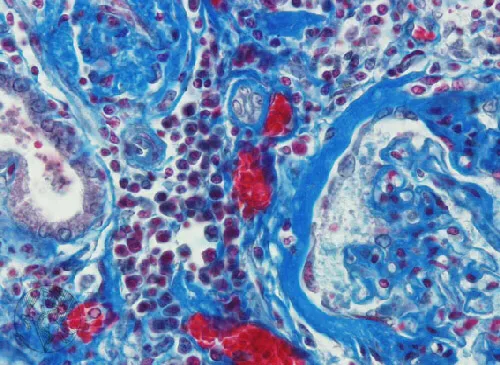

Injúria Renal Aguda (revisão Lancet 2025)

Injúria Renal Aguda (revisão Lancet 2025)